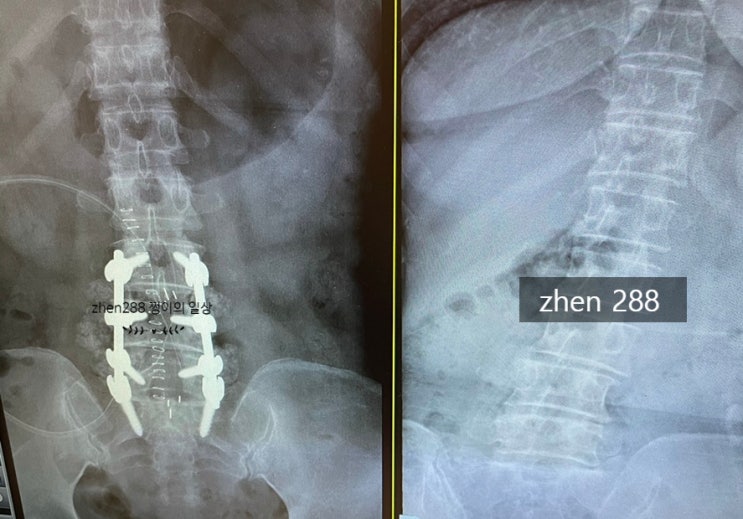

엄마 허리 척추 협착증 유합수술 경험 이야기 1.

사실 이 글을 올릴까 말까 고민을 많이 했는데 (너무 개인사인듯 하여 )... 나또한 수술하기 전에 워낙 대...

허리 척추 협착증 유합수술 경험 이야기 2.

23년 추가글 수술후 2년반 지난 후기 현재 23년8월, 많은분들이 수술후 어떤지 궁금해하시는거 같아서 짧게...